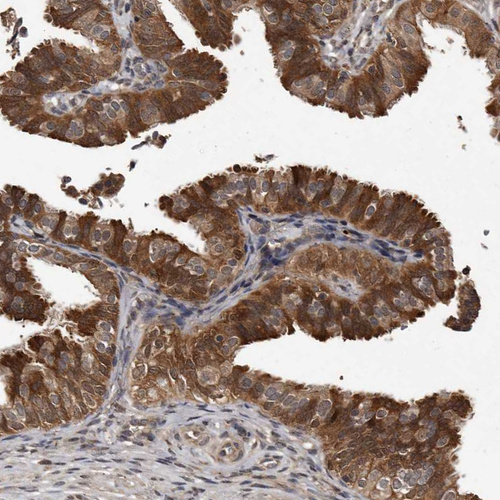

Immunohistochemical staining of human fallopian tube shows strong cytoplasmic positivity in glandular cells.